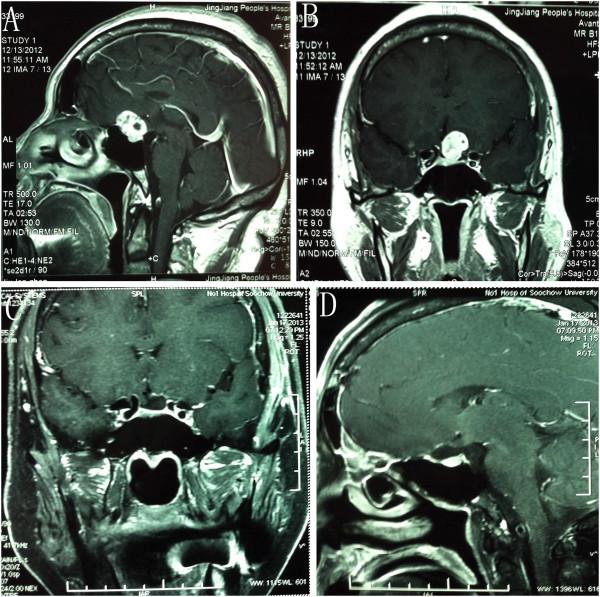

Between June 2011 and December 2011, 23 patients with neoplastic lesions underwent surgery by the corresponding author (ZW) via the LSO approach. The clinical presentations, neuroradiological findings, microsurgical techniques, and outcome at discharge of these patients were analyzed. In addition, the clinical series in the available literature written in English were also extensively reviewed. Eleven (48%) patients were treated for pituitary adenoma; six (26%) patients for tuberculum sellae meningioma; and six (26%) patients for craniopharyngioma.

Seemingly complete tumor removal was achieved in 21 patients (91%); surgical mortality was one patient (4.3%). Postoperatively, no patient had developed cerebrospinal fluid leakage or new visual deficits. One (4%) patient had intracranial infection, and one (4%) had a postoperative hematoma. The median Karnofsky score at discharge was 87.4 (range, 0 to 100). The Glasgow outcome scale at discharge was 4.6 (range, 1 to 5). Of all, 21 (91.3%) patients achieved favorable outcomes.